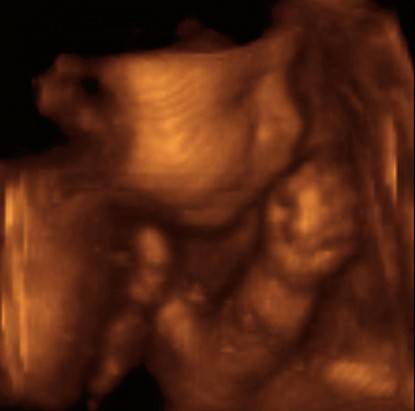

Un tipo particolare di ecografia morfologica è la 3D, ossia la tridimensionale, in cui sarà bellissimo ed emozionante vedere il nostro cucciolo di uomo.